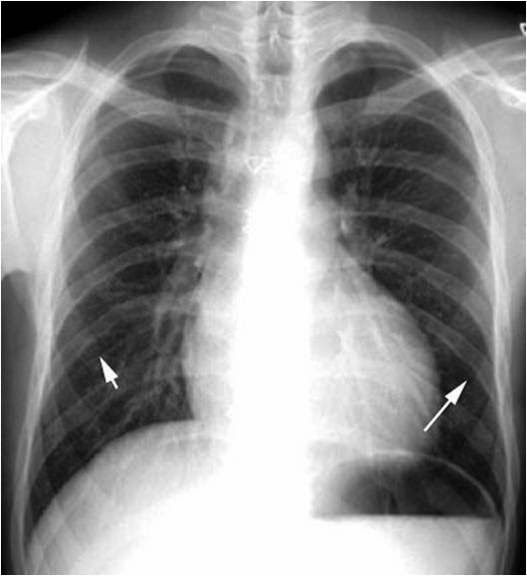

Chest radiography Rib notching (white arrows). Download Scientific Rib Notching Definition Rib notching are deformities that affect the upper surface of the rib, the lower surface of the rib (roesler’s sign), or both. Normal variants and abnormalities of the ribs are frequently encountered on chest radiographs. Acute rib infections are seen as focal areas of bone destruction, whereas chronic infections may manifest as periosteal reaction or a bone sequestrum. This article. Rib Notching Definition.